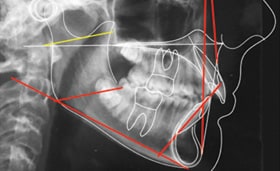

Non-compliance biomechanics and precise 3D control used to accomplish the planned treatment outcome.